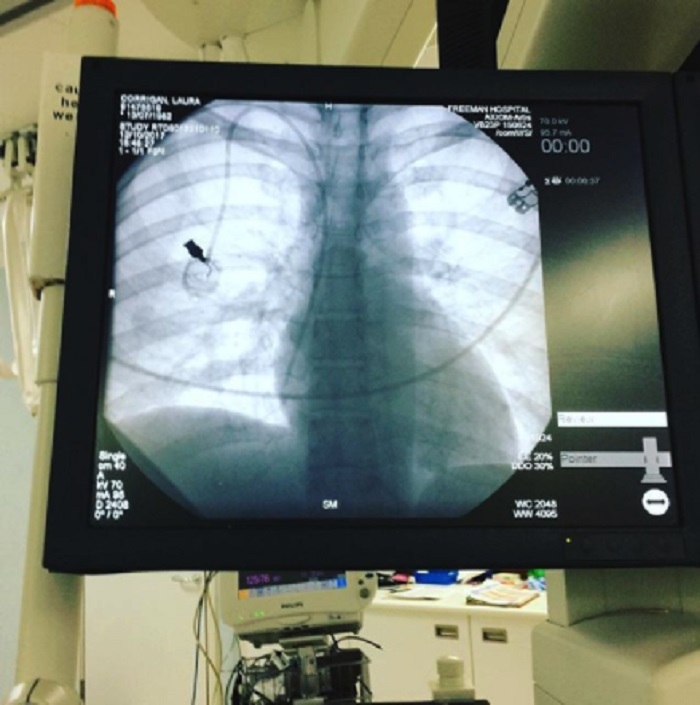

«Esta imagen fue tomada por mi hijo», escribió Laura Corrigan.

«Completo agotamiento. Esto fue cuando me sometí a radioterapia y quimioterapia», dijo.

La mujer tiene un cáncer intestinal que se ha diseminado a los pulmones, por lo que se somete a quimioterapia. Además de Max, Laura también tiene un hijo pequeñito, llamado Finn. Ella los educa y cría sola, con sus propios esfuerzos.

Esta mujer de 36 años de edad fue diagnosticada con cáncer el año pasado, después de quejarse de dolor intestinal y encontrar sangre en sus deposiciones.